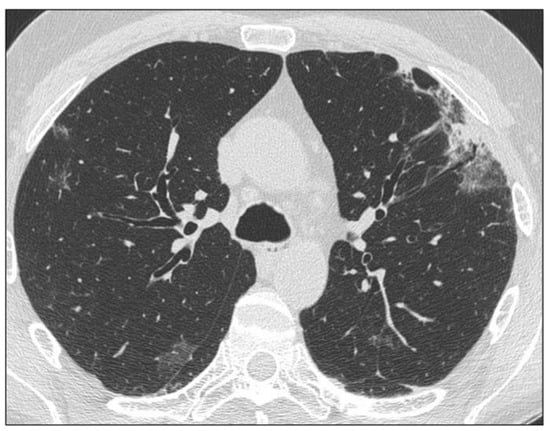

3.1.1. Ground Glass Opacities

3.1.4. Reticulations

3.1.5. Bronchiectasis/Bronchiolectasis